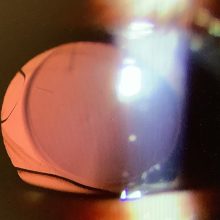

白内障手術後の相談にいらした40代前半の方は、今年の5月にレンティス・コンフォートを使った右眼の白内障の手術を受け、夜の光のグレアが気になるということで、予約をいただいておりました。